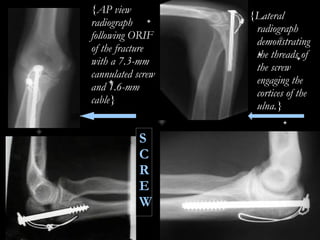

{AP view radiograph following ORIF of the fracture with a 7.3-mm cannulated screw and 1.6-mm cable} {Lateral radiograph demonstrating the threads of the screw engaging the cortices of the ulna.} S C R E W

{AP view radiographfollowing ORIF of the fracture with a 7.3-mm cannulated screw and 1.6-mm cable} {Lateral radiograph demonstrating the threads of the screw engaging the cortices of the ulna.} S C R E W